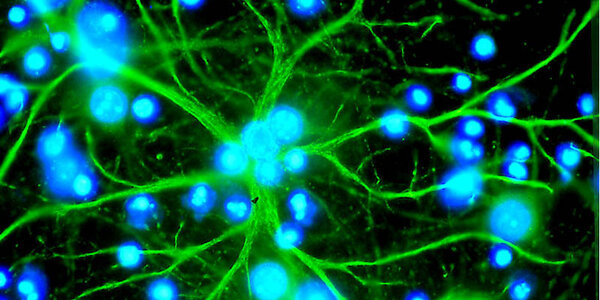

Childhood Abuse May Result In Structural Brain Changes

New research using magnetic resonance imaging (MRI) shows that abuse or emotional neglect during childhood combined with genetic factors can result in structural brain changes, rendering some individuals more vulnerable to  depression. The study results appear in Neuropsychopharmacology. 24 patients (aged 18-65 years) being treated as inpatients for major depression were investigated with high-resolution structural MRI and childhood stress assessments. Special analysis programs were used to measure brain regions. These patients were compared with 27 healthy control subjects from the…